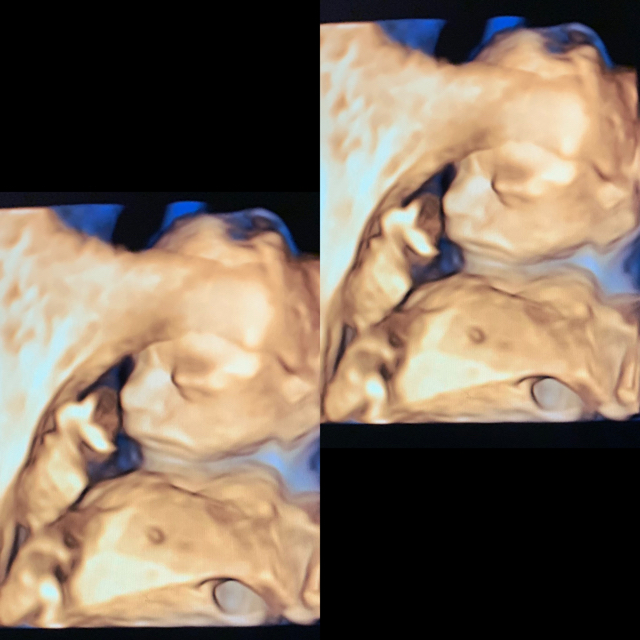

Im 20 weeks pregnant with a baby girl ❤️ what name sounds better Leilani Itzá Acevedo Cruz , or Leilani rose Acevedo Cruz ?